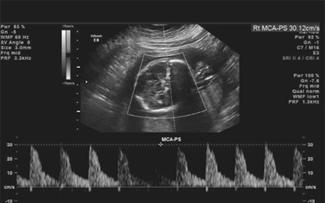

La ecografía doppler se reserva para estados fetales que muestren compromiso hemodinámico (fetos anémicos, RCIUs, gemelares monocoriales, preeclampsias, pretérminos severos), con la finalidad de detectar precozmente la insuficiencia placentaria y la hipoxia fetal. Se evalúan los siguientes vasos:

Los hallazgos patológicos son ↓ flujo en arteria umbilical, ↑ flujo arteria cerebral media, Notch proto diastólico en arteria uterina y flujo reverso en ductus venoso.